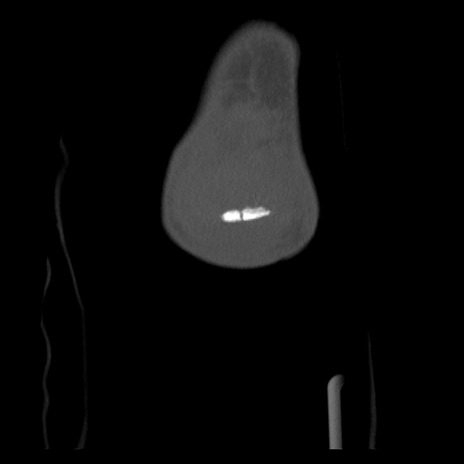

右膝関節CT

横断像